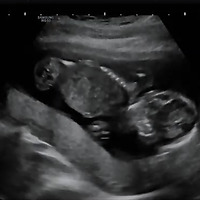

이번에는 일반 초음파뿐 아니라 입체 초음파도 예약되어 있어서 많은 기대를 하였다. 입체 초음파의 경우 일반 초음파보다 태아를 더 면밀하게 확인이 가능하고, 흑백으로 나오는 것이 아닌 주황빛을 띄는 이미지를 보여주기 때문에 기대가 되었다.

일반 복부 초음파를 보면서 의사가 태아의 성장을 확인하고 나면 입체 초음파는 따로 초음파 검사실에 있는 초음파실 선생님이 확인한다. 입체 초음파를 시행하는 경우 태아의 상태에 따라 소요시간이 달라진다. 아기가 자신을 잘 보여준다면 금방 끝이 나지만 손으로 얼굴을 가리는 등의 잘 보여주지 않을 경우 오래 걸리기도 하고 다음번에 다시 한번 초음파를 확인하기도 한다.

입체 초음파 또한 복부초음파처럼 침대에 누워 태아의 상태를 확인하는데 정밀검사처럼 태아의 손, 발뿐 아니라 얼굴 생김새까지 확인이 가능하다.

바른 자세로 누워 초음파를 시작했다. 손가락, 발가락뿐 아니라 양측 귀까지 입체 초음파를 통해 확인하고 태아의 얼굴 생김새를 확인했다. 일반 초음파로 확인할 때와 다르게 입체적으로 보이는 태아의 모습에 신기했다.